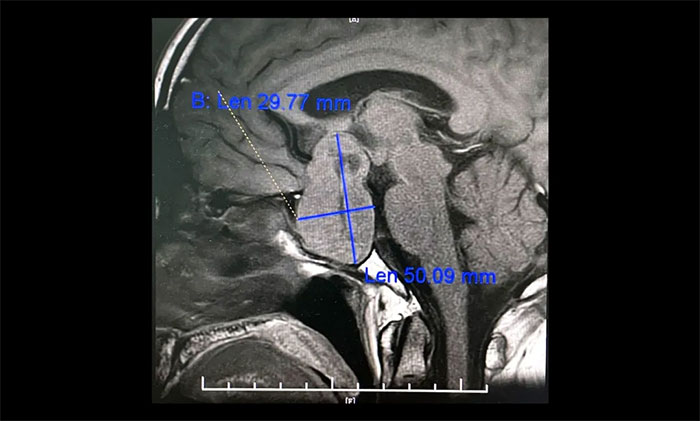

▲ 5公分巨大垂体瘤,呈“哑铃”形,李士其教授团队迎难而上顺利切除

李士其教授分析,对于病变已经侵袭海绵窦,单纯采用以往经鼻入路或经颅入路的术式均难以全切肿瘤,并且颈内动脉损伤的风险极大。如何将颈内动脉损伤风险降到最低,又能尽可能全切肿瘤?一般考虑采用经蝶和经颅联合入路手术策略切除肿瘤。

目前联合入路切除垂体瘤通常有两种方式,一是采用联合入路一次手术实现肿瘤全切除,二是分次手术以达到肿瘤切除的目的。李士其教授介绍,此类手术,对患者的视力保护极其重要,对于巨大垂体瘤难以一次性手术切除的肿瘤,可以先行一次手术,然后在数周或数月后执行进行二次手术,即经蝶和经颅联合入路分次手术策略。

李士其教授指出,因肿瘤组织多数较软,鞍内减压后,鞍上及海绵窦内肿瘤常可向鞍内塌陷。如术中塌陷不满意可暂予观察,一般1-3月后复查肿瘤可大部落入鞍内,可再次经蝶手术进一步切除。如仍不塌陷可考虑开颅手术,此时开颅手术难度及风险降低,而鞍底组织已愈合,一般不必担心脑脊液漏。